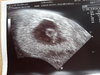

Witam sie z ciotkami to ja piekny maly 6cm czlowiek [emoji173][emoji173]

Z pieknie bijacym serduszkiem 126 uderzen na min

Super Gosiu. Tylko 6 cm to ok 12tc będzie